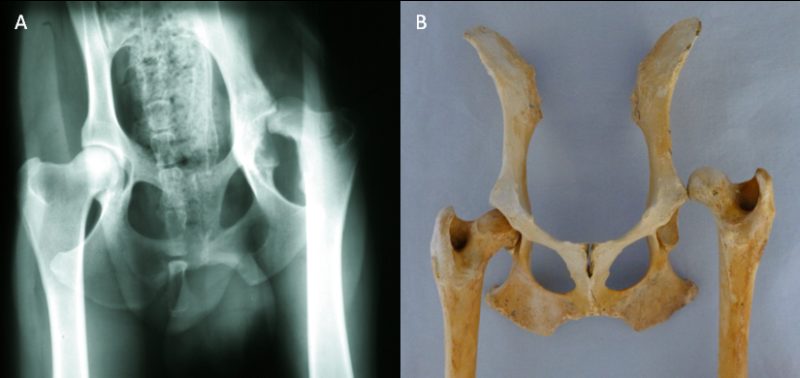

"Tyler", ein Dobermann-Mix, wurde am 18. August 2011 vom Nümbrechter Tierschutzverein "Menschen für Tiere e.V." in der Praxis vorgestellt mit dem Hinweis, er habe große Probleme mit seiner Hüfte und könne nur sehr schlecht laufen. Er war abgemagert bis auf die Knochen, lethargisch und litt sichtbar unter Schmerzen. Tyler zeigte einen deutlichen Muskelabbau und einen Hochstand des rechten Oberschenkels. Bei der Ganguntersuchung ist uns eine starke Lahmheit dieses Beines aufgefallen. Der Bewegungsumfang des Hüftgelenkes war deutlich eingeschränkt und bei der Streckung zeigte der Hund Schmerzen. Daraufhin haben wir eine Röntgenuntersuchung durchgeführt, wobei sich herausstellte, dass die Hüfte luxiert war, mit anderen Worten: der Oberschenkelkopf saß nicht in der richtigen Position. In einer funktionierenden Hüfte sitzt der Oberschenkelkopf in der Pfanne (s. Abb. 1). Bei Tyler saß der Oberschenkelkopf oberhalb der Pfanne. Er wies diese Veränderung seit langer Zeit auf, so dass der Oberschenkelkopf eine Pseudopfanne im Becken gebildet hatte (s. Abb. 2).